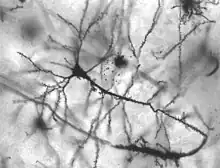

Neurological disorder

Neurons in person with epilepsy, 40x magnified